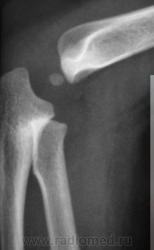

Я думаю, норма. Смутила линия просветления в заднем отделе метафиза плечевой кости. Но жировые подушечки в норме. Думаю, нет костно-травматических изменений.

Возможно я ошибаюсь, но так называемые "жировые подушечки", смещенные проксимально свидетельствуют о гемартрозе, но отнюдь не являются признаком наличия или отсутствия перелома.

По всей видимости, "эти подушечки" также как-то среагируют при наличии другой жидкости (не крови), если, она имеется в "определенном" количестве. Если, я не прав, то поправьте меня, я буду только Вам благодарен.

Смещение жировых подушечек (гемартроз) является косвенным признаком внутрисуставного перелома. Я, с некоторых пор, стала обращать на них прицельное внимание. При переломе они всегда смещены. А если я вижу их смещение, а явных признаков перелома не вижу, то пишу, что это является косвенным признаком перелома.

Полностью согласен с Вами, что, так называемые "смещенные" жировые подушечки, или просто жировые подушечки - это косвенный признак перелома, вернее признак гемартроза. Но, вот интересно всегда-ли они "смещаются" проксимальнее даже при гемартрозе?